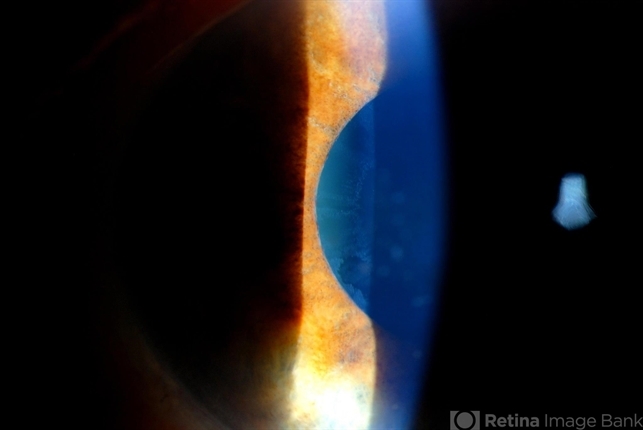

- Photo slit lamp biomicroscope

- Patient's VA 20/50 with pinhole no improvement. Patient will have cataract surgery in the future. Notice pseudoexfoliation ring centrally.